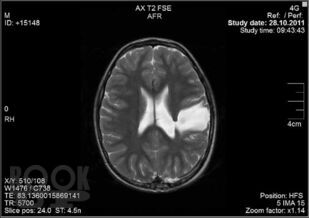

Изображения 14